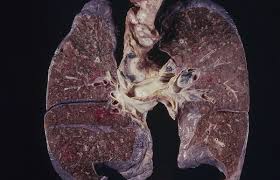

3. 폐암 초기증상이 나타나는 이유 🧬⚠️

폐암은 기관지나 폐 조직이 종양에 의해 막히거나 압박되면서 증상이 나타납니다. 암이 커지면서 혈관·신경을 침범하면 혈담, 흉통, 호흡곤란이 동반됩니다.

초기에는 감기·기관지염과 비슷해 진단이 늦어질 수 있습니다.